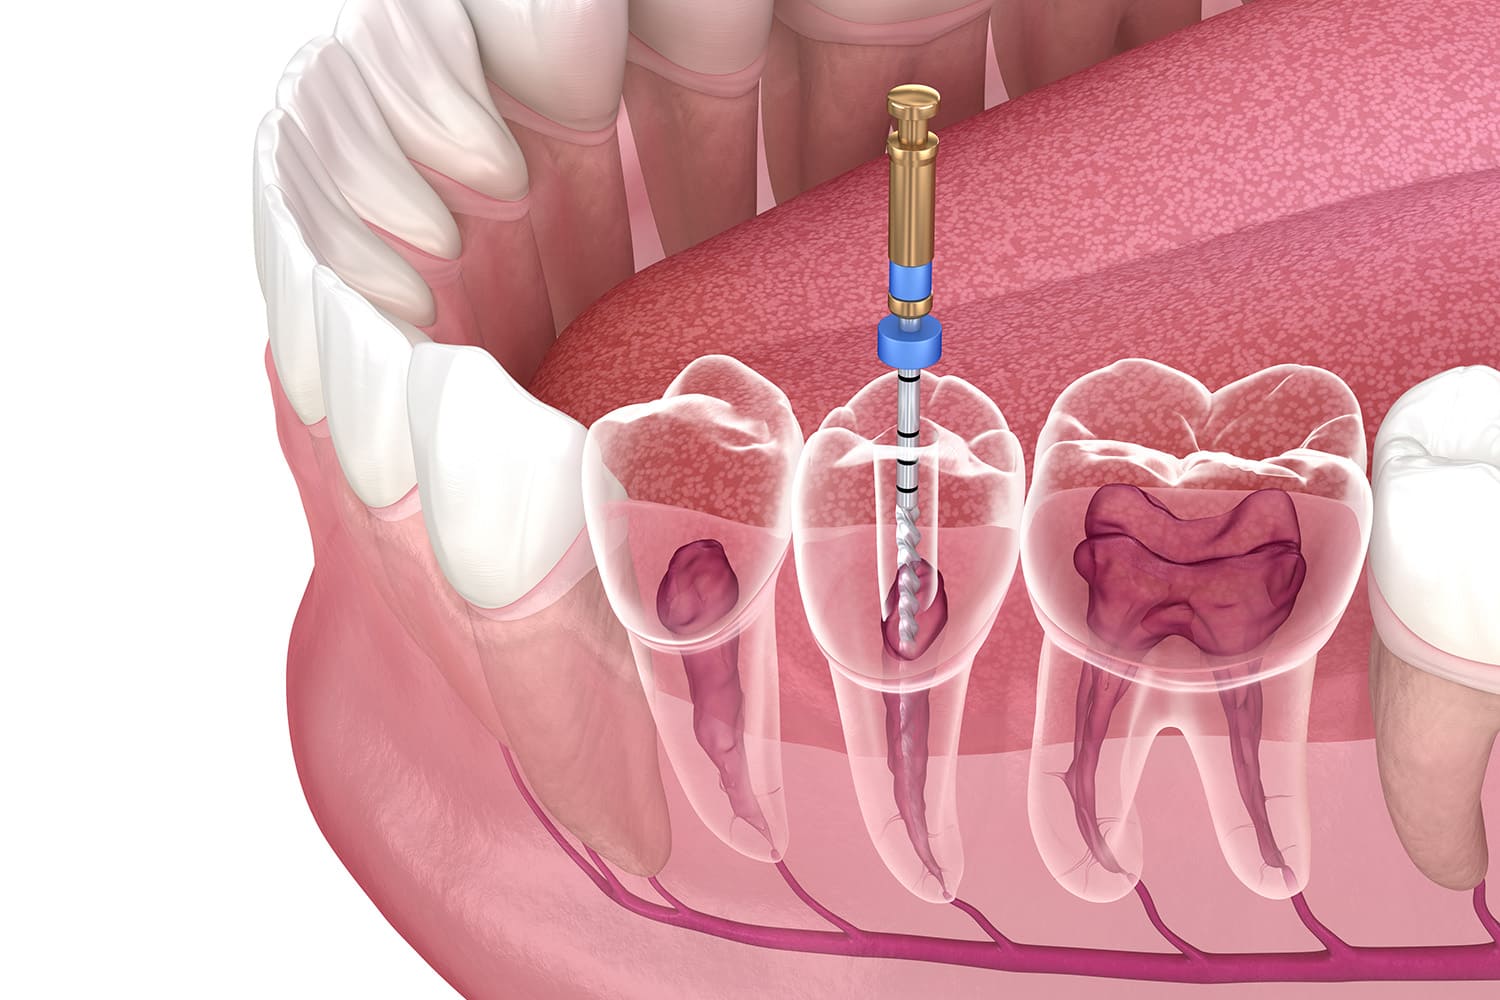

そしてどの処置も、再び治療の必要がないように丁寧に診査・診断を行います。治療の際には拡大鏡やマイクロスコープを使って慎重に歯を削り、精巧な型をもとに、患者さんのための詰め物をご用意します。